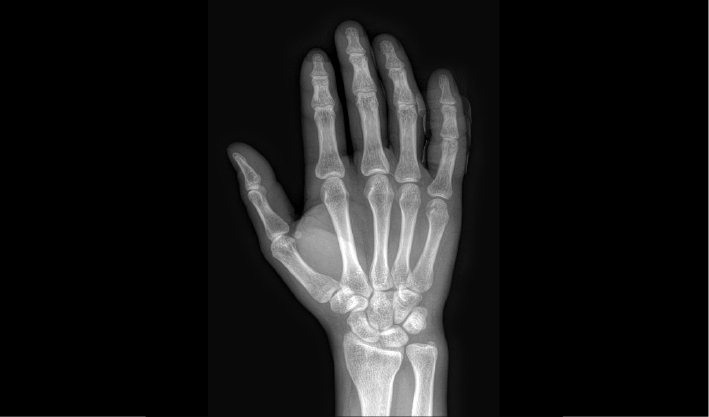

配合十軸智能全自動操控,實現六向跟蹤和一鍵自動擺位切換,融合高端配置,帶來一流的圖像,簡便操控,快捷流程,輔助醫生快速精準診斷。

消除線噪聲的同時不損失圖像細節,保持邊緣和分辨率,不會引入新偽影,增加圖像銳利度。

兩塊平板組合運用多種場景,減少平板插拔,簡化流程,提升拍攝效率。

管球無位移,消除運動誤差,提高拼接成功率。

重疊區域面積小,減少曝光次數,減少輻射劑量。

AEC自動曝光和影像均衡算法,保證拼接圖像統一亮度和對比度。